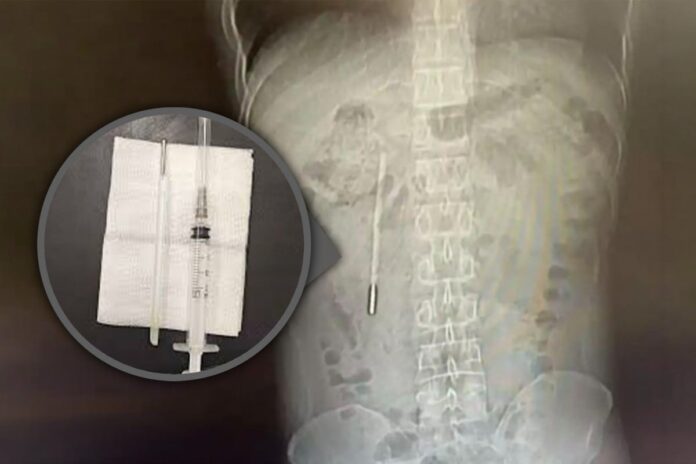

Theo kết quả từ các biện pháp chẩn đoán hình ảnh và chụp chiếu, các bác sĩ chuyên khoa đã phát hiện một dị vật nằm sâu bên trong tá tràng của bệnh nhân. Căn cứ vào hình dáng và đặc điểm trên phim chụp, đội ngũ y tế đã đặt ra nghi ngờ rất lớn rằng vật thể lạ này chính là một chiếc nhiệt kế thủy ngân.

Tình trạng lúc bấy giờ được đánh giá là vô cùng nguy hiểm. Phần đầu nhọn của chiếc nhiệt kế đang trong trạng thái ép trực tiếp vào lớp thành ruột của bệnh nhân. Vị trí và tư thế này đặt ra một nguy cơ cực kỳ cao về việc gây thủng ruột và dẫn đến tình trạng chảy máu trong nghiêm trọng, đe dọa trực tiếp đến tính mạng của người bệnh nếu không được can thiệp kịp thời.

Nhận thức được mức độ nghiêm trọng của ca bệnh, các bác sĩ phẫu thuật đã nhanh chóng triển khai một ca mổ khẩn cấp. Quá trình can thiệp y tế để lấy dị vật ra khỏi cơ thể chỉ diễn ra trong vòng hai mươi phút ngắn ngủi nhưng lại đòi hỏi sự tập trung cao độ.

Rất may mắn, thiết bị được lấy ra vẫn còn giữ được hình dạng nguyên vẹn ban đầu, mặc dù các vạch đo nhiệt độ in trên thân nhiệt kế đã bị mờ nhạt đi theo thời gian do tác động của môi trường dịch vị.

Các bác sĩ tại bệnh viện liên kết đầu tiên thuộc đại học y khoa Ôn Châu đã phẫu thuật khẩn cấp hai mươi phút để lấy dị vật.